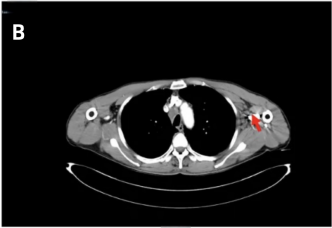

颈部、胸部、腹部增强CT:右肺下叶占位较前缩小,现约25mm×22mm(图4A);左腋窝淋巴结较前缩小(图4B)。

头颅增强MRI及DWI:左侧额叶原有病灶较前增大(图4C),左侧颞枕叶交界区见新发病灶(图4D)。

图4 右肺病灶、左侧腋窝淋巴结及颅脑病灶复查结果(红色箭头指向病灶)[1]